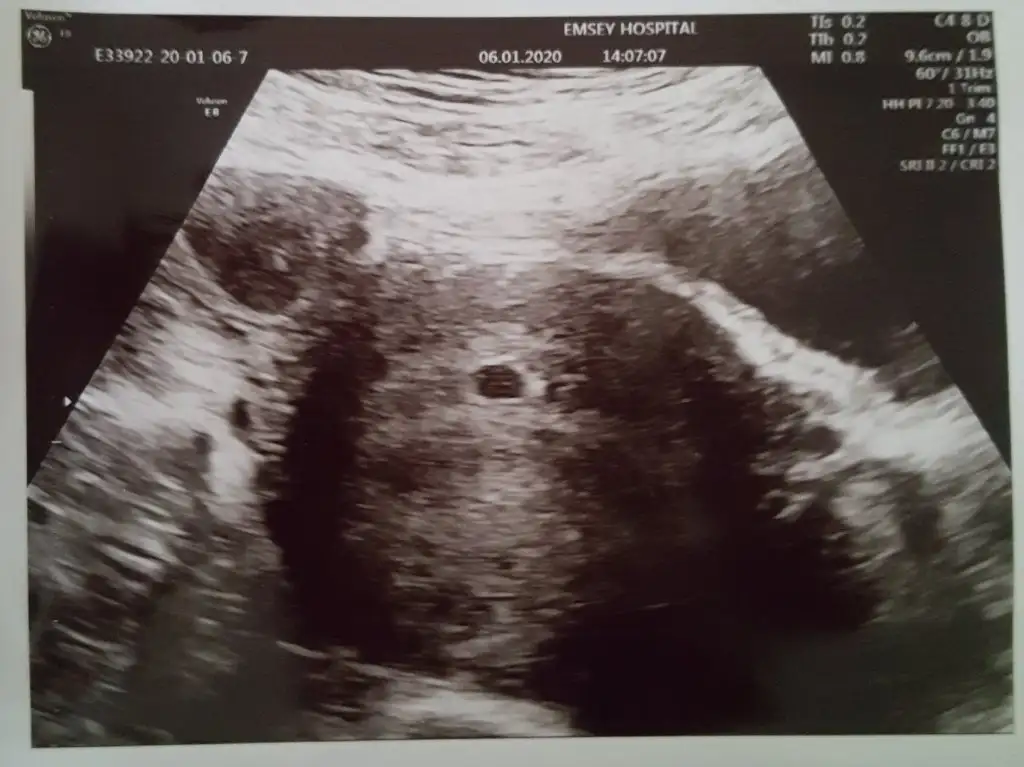

Ben bugün keseyi gördüm mesela, hem de daha 18. günde, hem de karından 😀

Eklentiler

• 20200106_151621.webp

20200106_151621.webp

30 KB · Görüntüleme: 186

Maşallah maşallah Allah nazarlardan korusun kalp atışı peki duydun mu? Bir adet sanırım?

Yok canım daha kesenin içini de göremedim çünkü daha çok ufak. Haftaya pazartesi yeniden bakılacak, iki embriyo transferi olmuştum, erken olduğu için ikincisi varsa da şimdi görünmez dedi o zaman netleşecek. Daha kalp atışına var yani 😊